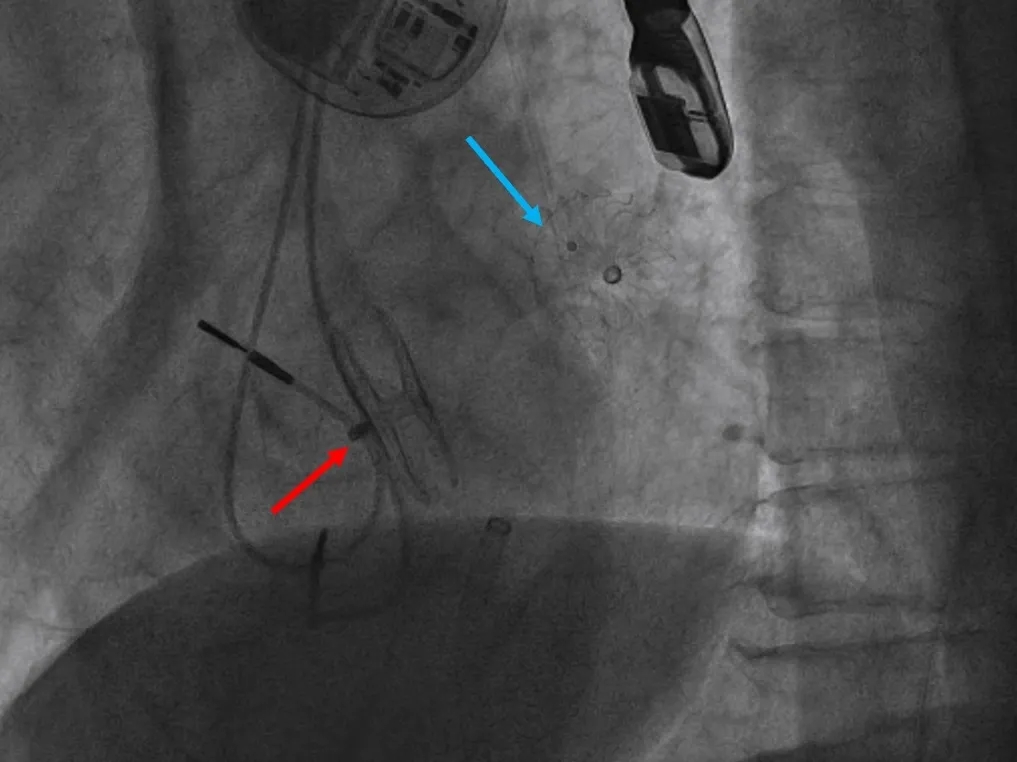

多学科讨论,为了尽可能降低卒中发生风险,平衡卒中与出血的矛盾,决定采取同期完成左心耳封堵与ASA/PFO封堵的“一站式”策略,穿刺点选择是该介入治疗的关键。在TEE实时引导下,选择ASA中心为穿刺点,并未经PFO进入左心房。这样不仅可改善左心耳封堵的同轴性,还可实现对ASA及PFO的完整覆盖,避免人为制造新的房间隔缺损。

TEE引导下的房间隔穿刺